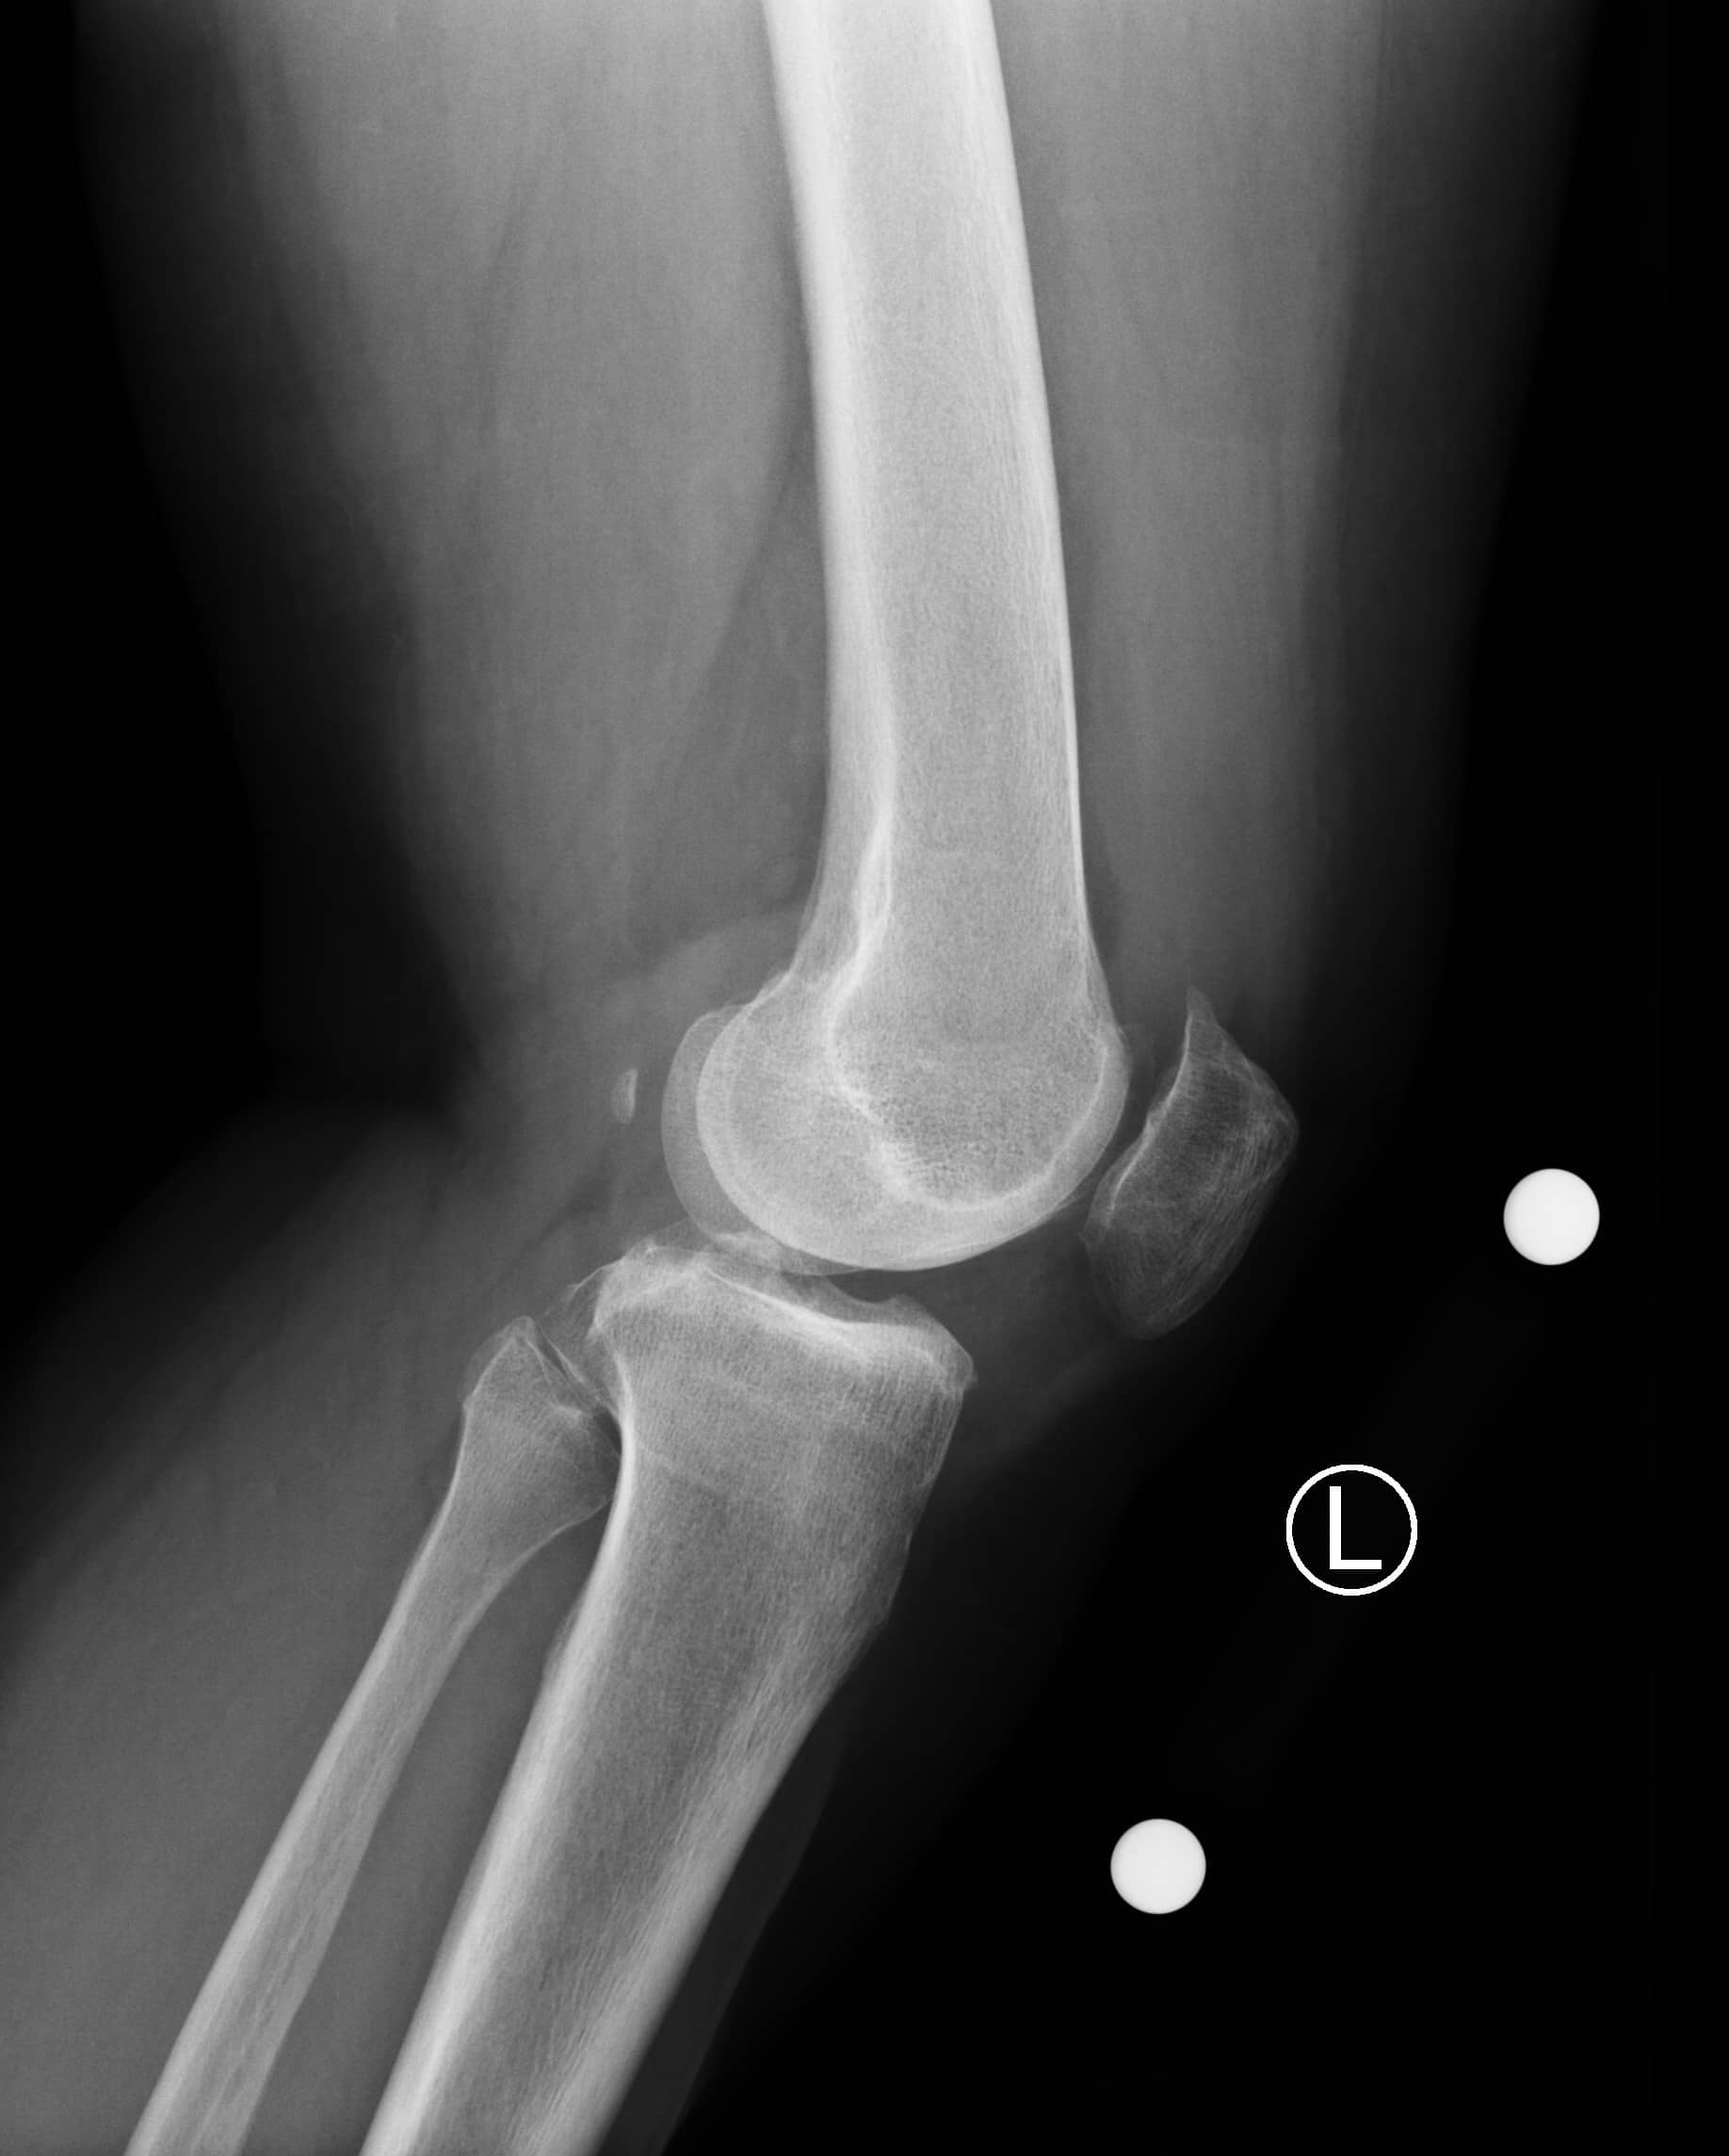

रोगी एक 66 वर्षीय महिला है जो चोट या आघात के इतिहास के बिना बाएं घुटने के दर्द के 2 साल के इतिहास के साथ प्रस्तुत करती है। दर्द लंबे समय तक अनुकरण, सीढ़ियों पर चढ़ने और लंबे समय तक खड़े रहने से बढ़ जाता है। आजमाए गए उपचारों में ब्रेसिंग, विरोधी भड़काऊ मौखिक दवाएं, अच्छी अस्थायी राहत के साथ कॉर्टिकोस्टेरॉइड इंजेक्शन और औपचारिक भौतिक चिकित्सा शामिल हैं। उसके पास उच्च रक्तचाप, हाइपरलिपिडिमिया और चिंता का पिछला चिकित्सा इतिहास है।

रोगी आरामदायक, अच्छी तरह से दिखाई देने वाला और समय, स्थान और व्यक्ति के लिए उन्मुख था। वह एक एंटाल्जिक चाल के साथ घुलमिल गई। उसके बाएं निचले छोर की जांच से पता चला कि त्वचा साफ और बरकरार थी। जांघ और पैर के डिब्बे नरम थे। उसे दर्द के बिना गति की एक सामान्य कूल्हे की सीमा थी। मोटे तौर पर, उसके घुटने हल्के वरस विकृति में थे। एक मध्यम घुटने का बहाव था। उसके घुटने की गति 0 ° से 115 ° तक फ्लेक्सन थी। उसे औसत दर्जे की संयुक्त रेखा पर कोमलता थी। उसके घुटने की लिगामेंट परीक्षा पूर्ववर्ती दराज, लाचमैन, पश्चवर्ती दराज, और वरस और वाल्गस तनाव परीक्षण के लिए स्थिर थी। उसका एक्सटेंसर तंत्र बरकरार था, और उसे सीधे पैर उठाने के साथ कोई दर्द नहीं था। वह न्यूरोवास्कुलर रूप से दूर से बरकरार थी।

कुल घुटने के आर्थ्रोप्लास्टी (टीकेए) के साथ आगे बढ़ने का निर्णय लेने से पहले महत्वपूर्ण रेडियोग्राफी में वजन-असर एपी, पीए फ्लेक्सन, पार्श्व और सूर्योदय दृश्य शामिल हैं। कुछ सर्जन लंबे पैर संरेखण रेडियोग्राफ की समीक्षा करना भी पसंद करते हैं। इस रोगी के लिए छवियों ने हड्डी-पर-हड्डी संपर्क, सबकॉन्ड्रल स्केलेरोसिस और मल्टीपल पेरिआर्टिकुलर ओस्टियोफाइट्स के साथ मेडियल और पेटेलोफेमोरल डिब्बे में संयुक्त स्थान के नुकसान के साथ गंभीर अपक्षयी परिवर्तनों का खुलासा किया। हल्के वरस यांत्रिक संरेखण था। पटेला सूर्योदय के दृश्य पर केंद्रीय रूप से ट्रैक कर रहा था।